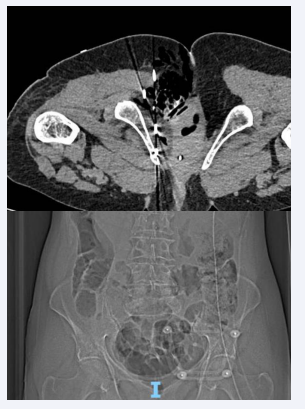

Following a multidisciplinary discussion, considering the significant pain symptoms severely affecting the patient’s quality of life, she was selected for cryoablation of the pelvic lesion (Figure 2-4), which was subsequently performed in January 2024. MRIs performed in February and April 2024 showed stable disease. Currently, the patient is under oncological follow-up, with significant pain relief managed by paracetamol and codeine.

Figure 4: Procedure of cryoablation of the pelvic lesion, with the formation at  an Iceball measuring 51 x 34 x 35 mm.